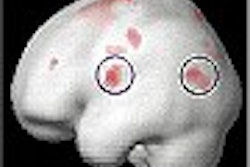

"Imaging has always been a problem in urology and prostate cancer," Djavan said. "Cancer has both neovascularization and hypoxia, and the perfusion pattern...is completely different from normal and benign tissue." The combined approach looks for patterns of neovascularization and hypoxia, he said. The study was a collaboration between investigators at the University of Vienna and the Weizman Institute in Tel Aviv.

The researchers analyzed the dynamic T1-weighted images with a 6-time-point and 3-time-point (3TP) pharmacokinetic model. Two independent readers evaluated the T2 and T1 images. They then correlated the MRI data with histopathologic results.

The histopathologically determined tumor stage was classified according to tumor size, lymph node involvement, and the status of metastasis (TNM). Using the T2-weighted images, the readers correctly assessed the TNM stage in 21 of 25 cases (8%). In two cases (8%), tumors were understaged. In two cases (8%), tumors were overstaged.

When they used the parametrically analyzed dynamic T1-weighted images, the readers staged the tumors accurately in 19 cases (76%). In six cases (24%), tumors were overstaged.

The combined approach allowed the readers to accurately stage the tumors in 23 cases (92%). In two cases (8%), tumors were overstaged. In addition, only the combined approach allowed a correct diagnosis of extracapsular disease in all 10 cases with that level of regional spread (100%), including five cases of seminal vesicle infiltration.